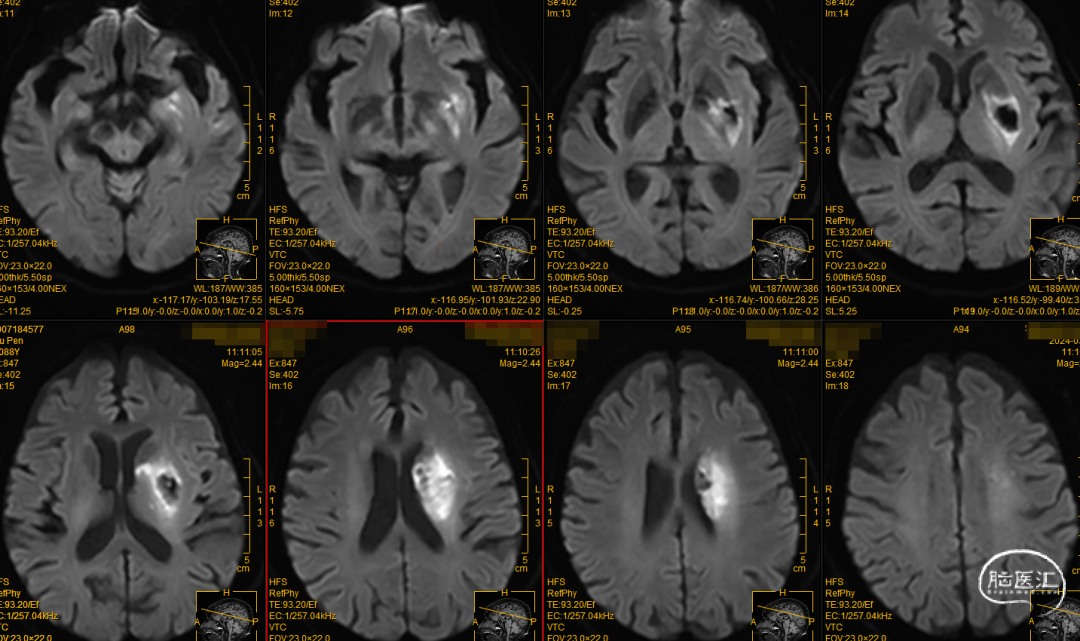

颅脑MRI